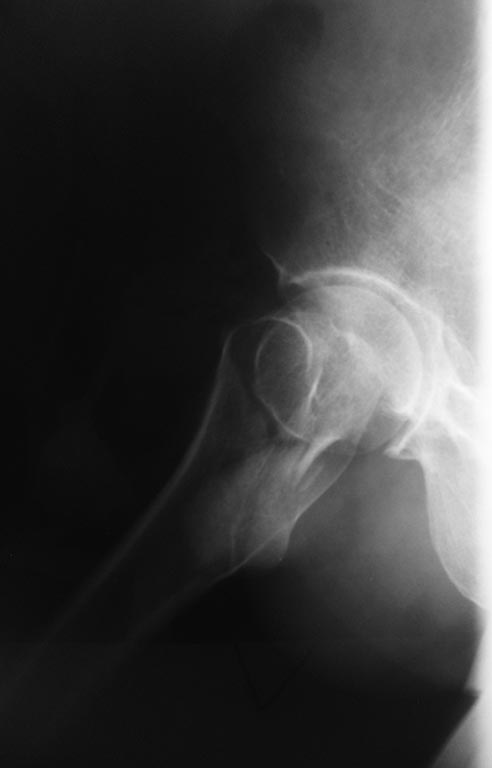

Не похоже на вколоченный перелом. Аксиальная проекция - красивая "художественная" иллюзия - хорошая.

Это Garden III-IV, так что у пациента мужского пола в этом возрасте надежнее эндопротезирование. Если по каким-то причинам этот вариант недоступен, то остеосинтез лучше сделать хотя бы не винтами, а каким-то из fixed angle implants - PFN, DHS, Targon FN...

Здесь даже намека нет на вколоченный перелом.